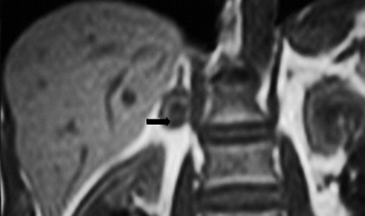

En la TC no contrastada las glándulas suprarrenales normales son homogéneas y simétricas, con una densidad muy similar a la del parénquima renal adyacente (Figura 1 a). Con un medio de contraste ev la glándula suprarrenal se opacifica en forma homogénea, similar al hígado o al bazo (Figura 1 b). Si la cantidad de tejido adiposo retroperitoneal es abundante las glándulas suprarrenales pueden aparecer enteramente rodeadas por grasa y su delimitación es más fácil (Figura 2 a); lo inverso ocurre en pacientes muy delgados con escasa grasa retroperitoneal (Figura 2 b). En RM, en secuencias ponderadas en T1 y T2 convencionales tienen una intensidad de señal homogénea, hipointensa respecto de la grasa adyacente e iso o hipointensa con respecto del parénquima hepático (Figura 3 a y b). En los cortes coronales se aprecia mejor la forma y la posición de las glándulas suprarrenales (Figura 3 c).

Figura 3. Glándula suprarrenal normal en resonancia magnética. (a) Cortes axial ponderado en T1 la señal de la glándula normal (flecha negra) es hipointensa respecto a la grasa retroperitoneal e isointensa respecto al parénquima hepático. (b) Cortes axial ponderado en T2 en que se muestra la glándula suprarrenal derecha (flecha blanca) y (c) corte coronal ponderado en T2 en que se muestra la glándula suprarrenal derecha (flecha blanca) y la glándula suprarrenal izquierda (flecha negra) con similares características de intendidad de señal. 3. Causas y prevalencia de las lesiones suprarrenales